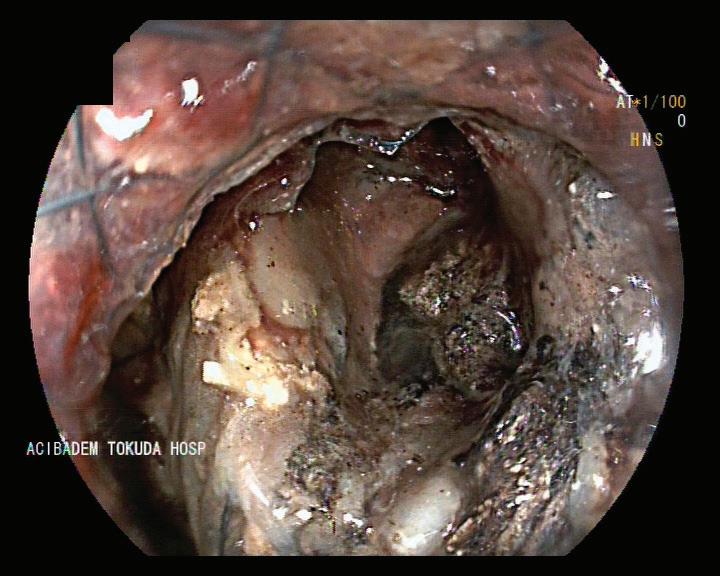

на СА19-9 и карциноембрионален антиген (СЕА) се прилага при пациенти със сус пектен злокачествен процес, като спомага за диагностиката и проследяването му, въпреки че не са специфични маркери за билиарна ма лигненост. При менажирането на такъв тип стенози от из ключителна важност е предварителното ста диране на пациента с образни методи – УЗ, КТ Фиг. 1 Холангиограма на пост оперативна стеноза след холецистектомия Фиг. 2 Холангиоскопски образ при стеноза на анасто мозата след чернодроб на трансплантация чини,

с контраст, магнитно-резонансна хо лангиопанкреатография – неинвaзи вен метод, който не само локализира интрахепаталните жлъчни стриктури (97% точност), но също така позволя ва създаването на карта „billiary map tree“, която да планира ендоскопска та интервенция Ендоскопски метод на избор при диференциална диагноза между бенигнен и малигнен характер на стенозата е ЕРХПГ с холангиоско пия – директна визуализация и оха рактеризиране, с възможност за це ленасочени биопсии и хистологична верификация. Чрез тези методи може да се установи локализацията, видът и протежението на стенозата. Инфор мативността и достоверността на тези два метода (ЕРХПГ и холангиоскопия) е близо до 100%[11] (Фиг. 2). Перкутанната трансхепатална холан гиография и сцинтиграфията в наши дни почти са изгубили диагностична стойност. Ендоскоспската ехография може да бъде полезна по отношение на деферинциална диагноза на ма лигнени лезии, причнияващи билиар на стеноза, както и в определени слу чаи за терапевтичен жлъчен дренаж при бенигнени стриктури на ЖП[1] ЛЕЧЕНИЕ Доброкачествените жлъчни стрик тури са предизвикателство за лече ние. Повечето бенигнени стриктури са свързани с хирургични процеду ри, травматична увреда на жлъчните пътища при чернодробна трансплан тация и лапароскопска холецистек томия, като съобщаваната честота варира съответно между 3 и 13% и меджу 0.2 и 0.7%[12].